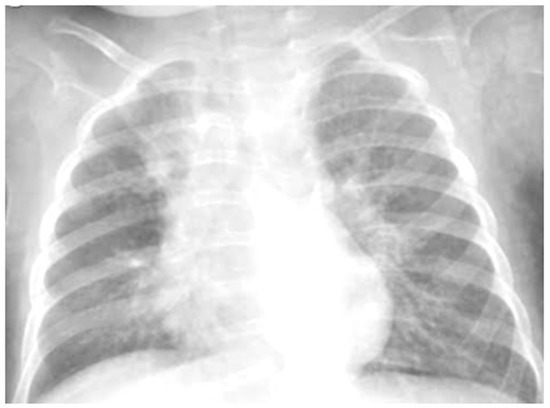

Case 6 was a 10-year-old girl with a medical history of allergic rhinoconjunctivitis recurring since childhood; her diagnosis of allergic asthma (T2-eosinophilic phenotype— “T2-high” [11,12]) was from 6 years of age. It has always been a severe phenotype despite adequate preventive therapy, so much as to require a progressive step-up of the therapy itself up to the maximum step [1,2,3]. Despite this, and the good adherence to therapy, she came to our attention at the pediatric allergy clinic of our hospital, reporting that she was still having recurrent symptoms, resorting daily to short-acting bronchodilators, and was also having nocturnal symptoms. She had an ACT of 20 points [13], and pathological control spirometry. Therefore, in consideration of the presence of severe eosinophilic T2 allergic asthma (T2-high), the patient was a candidate for the administration of a biological drug. However, before classifying the patient as such, a chest CT was performed to exclude the presence of other pathological respiratory conditions that could dissemble asthma (Figure 8).

Figure 8.

A representative coronal section from thoracic computed tomography (CT) scan reveals: thickening of the bronchial walls bilaterally, with filling of the bronchial lumen predominantly in the apical segment of the right upper lobe; picture of diffuse inhomogeneity of parenchymal density with diffuse and bilateral hypodense areas in relation to air trapping correlated to a picture of recurrent airway inflammation.

LUS was also performed, which showed a picture compatible with the features detected on CT (Figure 9).

Figure 9.

Grayscale lung ultrasound examination shows a picture of sonographic interstitial syndrome (SIS) represented by: (A): irregularity of the pleural line, short vertical artifacts, and long vertical artifacts unevenly distributed bilaterally; (B,C): irregularity of the pleural line, sub-centimeter consolidations associated with long confluent vertical artifacts located mainly in the right lung fields, mainly in the mid-apical area; (D,E): short vertical artifacts with pleural line irregularities unevenly distributed bilaterally.

Furthermore, evaluating some patients who had important ultrasound lesions (such as atelectasis of a certain entity, or diffuse sonographic interstitial syndrome), as in the first three cases, we wondered if some of these lesions may have already been present before the acute attack, and also in consideration of the finding of a positive ultrasound picture even in the stability phase, and after starting an adequate preventive therapy. Hence, there is a need to take into account the asthmatic phenotype and its severity for all patients, and also to evaluate the ultrasound patterns of patients in the stability phase in an outpatient setting, as in case 6. In the latter case—a patient with allergic asthma severe eosinophilic atopic type 2, but in a stability phase—the chest CT (Figure 8) showed signs of airway and lung parenchyma remodeling compatible with the patient’s severe clinical picture. LUS (Figure 9) showed a picture of diffuse short vertical artifacts, long confluent and non-confluent artifacts, and irregularities of the pleural line and sub-centimeter consolidations: lesions that, in the absence of acute respiratory pathology (as in our case), could be compatible with the remodeling pattern found on the chest CT.